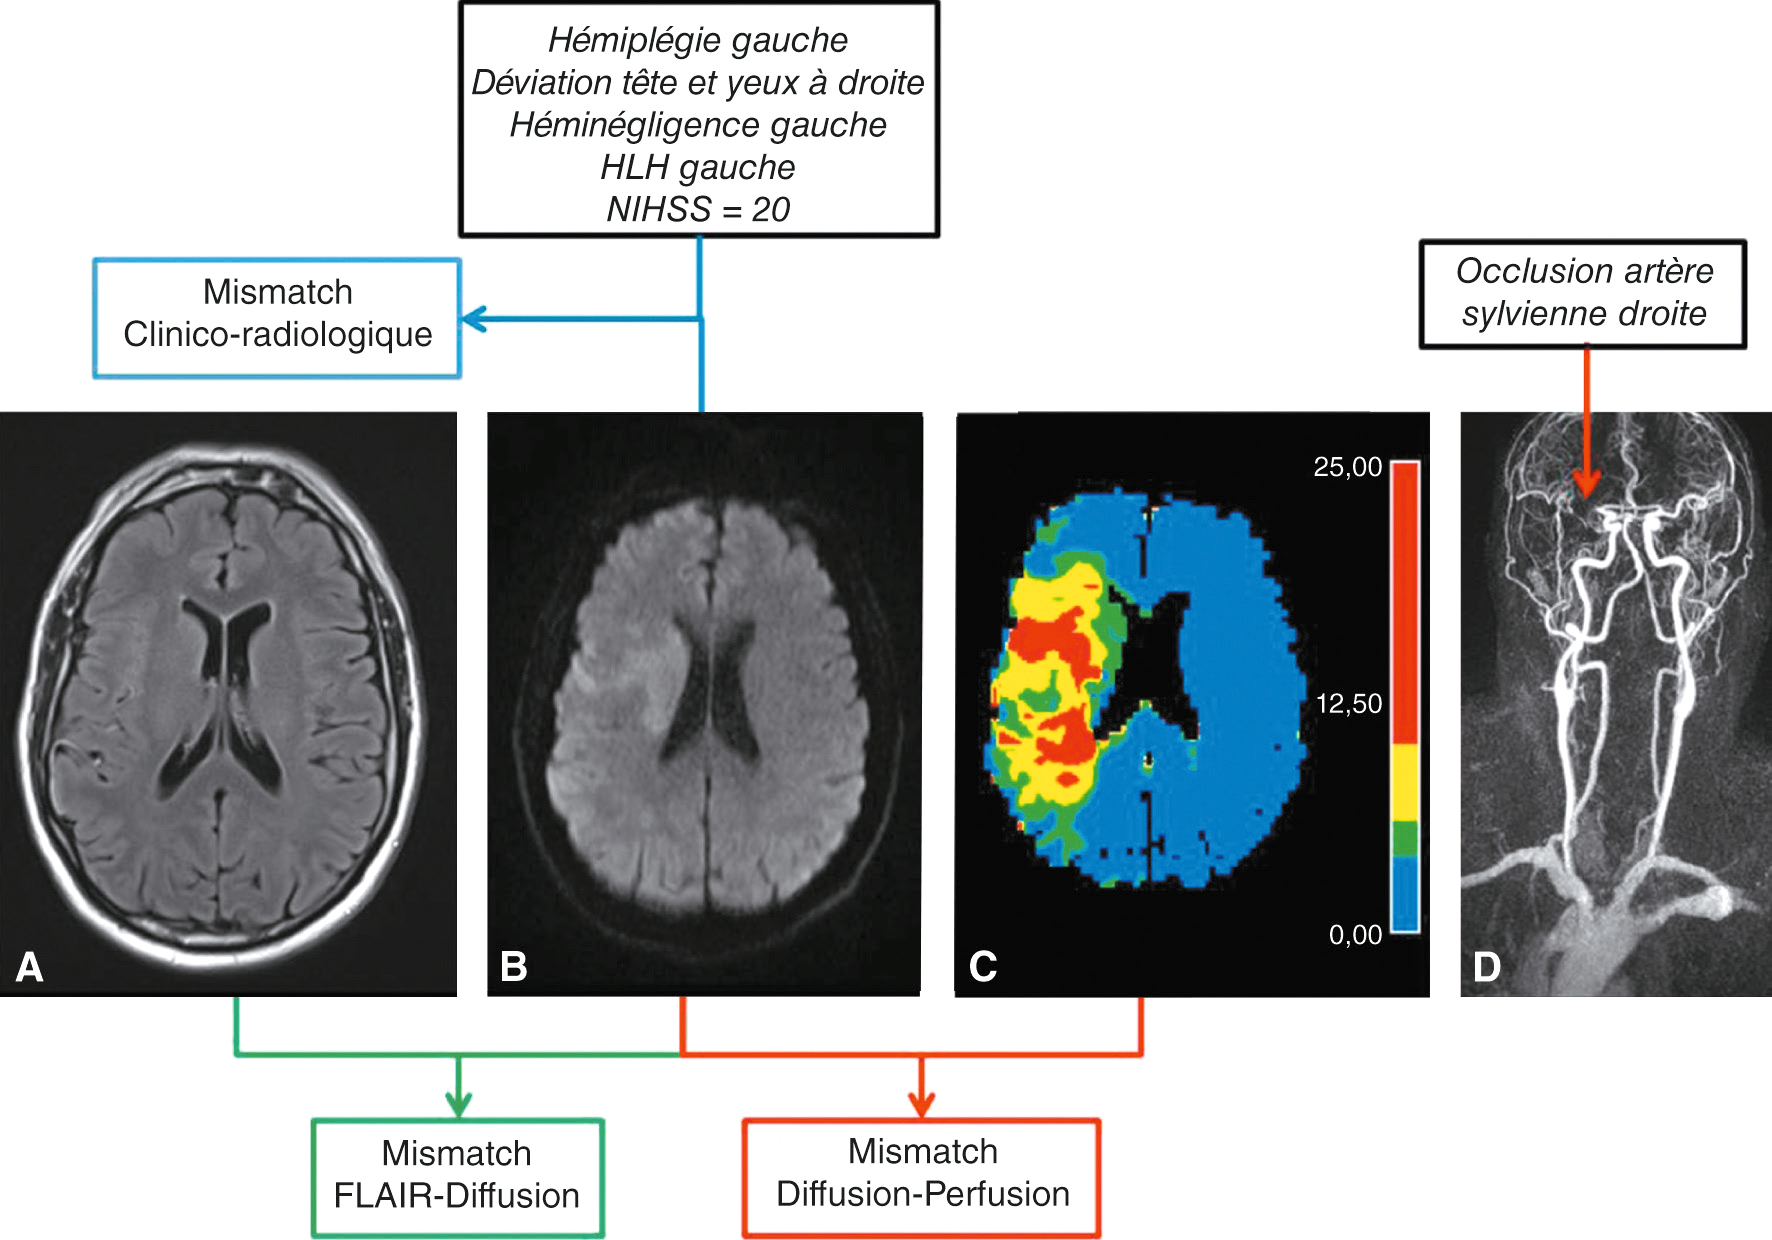

Fig. 28.12 Figure Les mismatchs. Identification des mismatchs témoignant :

• de l’existence d’un parenchyme à sauver de l’ischémie : 1. clinique/radiologique : clinique sévère (NIHSS = 20), volume d’infarctus faible en séquence IRM de diffusion (B) ; 2. diffusion/perfusion : volume d’infarctus faible en séquence IRM de diffusion (B) avec large volume d’ischémie en séquence IRM de perfusion (C) ;

• – du délai écoulé depuis le début des symptômes : 1. diffusion +/FLAIR – : lésion présente en séquence IRM de diffusion (B) sans anomalie sur la séquence IRM FLAIR (A) réalisée au même moment évoquant un délai probable de début des symptômes < 4 h 30; 2. diffusion –/FLAIR + : lésion négative en séquence IRM de diffusion avec anomalie sur la séquence IRM FLAIR réalisée au même moment évoquant un délai probable de début des symptômes > 15 jours.

• – elle permet aussi une mesure du volume de l’infarctus cérébral, contribuant à l’identification d’un « mismatch clinico-radiologique », qui permet d’identifier les patients éligibles à une stratégie de revascularisation au-delà de 4 h 30 après le début des symptômes (fig. 28.11 et 13);

• – l ‘existence d’une lésion sur la séquence de diffusion en l’absence de lésion sur la séquence FLAIR correspond à un « mismatch FLAIR-diffusion » qui traduit une ischémie datant probablement de moins de 4 h 30 (fig. 28.12);

• – perfusion, qui visualise la zone hypoperfusée. La soustraction entre perfusion et diffusion permet d’identifier la zone de pénombre où les lésions sont réversibles et qui 532constitue la cible des stratégies thérapeutiques de reperfusion. Cette séquence n’est à ce jour pas obligatoire au cours des infarctus pris en charge dans les 6 premières heures. Elle contribue à l’identification d’un « mismatch diffusion-perfusion » permettant d’identifier les patients éligibles à une stratégie de revascularisation endovascu-laire au-delà de la 6e heure après le début des symptômes (voir plus loin) (fig. 28.14A et 28.15).